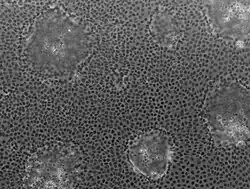

Microscopically, Caco-2 cell cultures show obvious heterogeneity likely reflecting the complex mixture of cells found in the epithelial lining of the large and small intestine i.e. enterocytes, enteroendocrine cells, goblet cells, transit amplifying cells, paneth cells and intestinal stem cells.[5] Over time, the characteristics of the cells used in different laboratories have diverged, introducing inter-laboratory variation.[6] Despite such heterogeneity, Caco-2 cells are used in cell invasion studies, viral transfection research, and lipid transport.[7]

Caco-2 cells may be used as a confluent monolayer on a cell culture insert filter (e.g., Transwell). In this format, Caco-2 cells form a polarized epithelial cell monolayer that provides a physical and biochemical barrier to the passage of ions and small molecules.[4][8] The Caco-2 monolayer can be used as an in vitro model of the human small intestinal mucosa to predict the absorption of orally administered drugs. Kits, such as the CacoReady, have been developed to simplify this procedure.[9] A correlation between the in vitro apparent permeability across Caco-2 monolayers and the in vivo fraction absorbed has been reported.[10] Transwell diagram